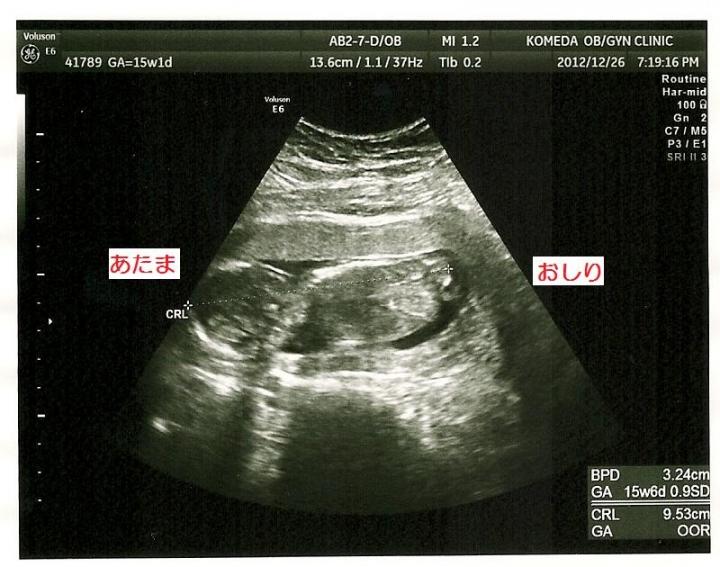

そして昨日、定期健診に行ってきました(^^)

15週と1日(^^)

頭からお尻まで 9cm (^^)

カメラに背を向けていました(;;)性別は分からず(;;)

エコーの最中 少しだけお尻を ふりふり☆ してました(笑)

主人は性別を知りたくないらしく、エコーに立ち会いはしなかったのですが、あとから 写真をみて

『命名 こけし 』と言ってまいた(笑)